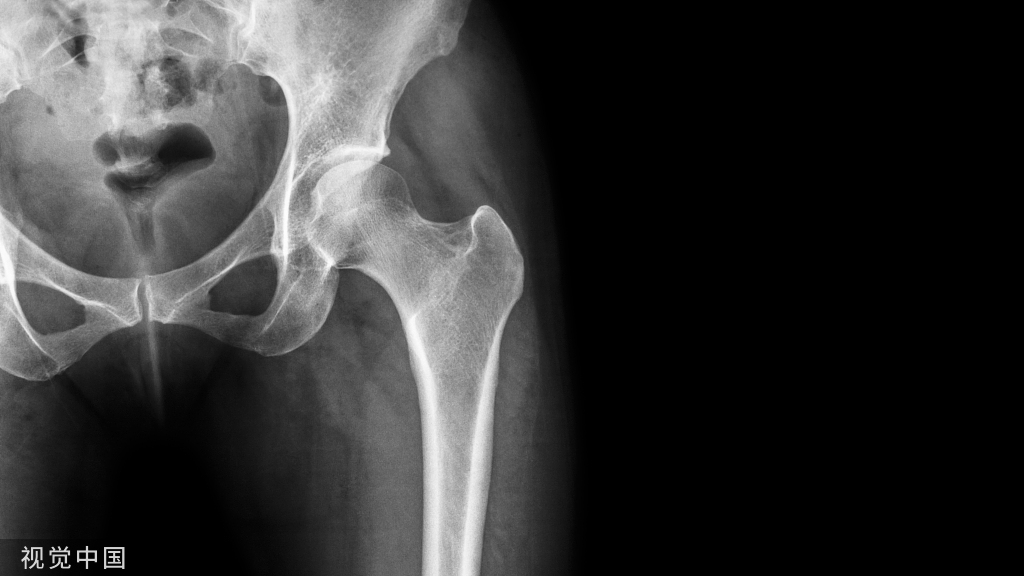

1. 优点(1)技术先进:进口骨科内固定装置通常采用先进的材料和技术,确保了装置的稳定性和耐用性。(2)设计合理:进口骨科内固定装置的设计更加符合人体工学和骨骼的力学,能够减少手术时间和术后并发症的风险。(3)质量可靠:进口骨科内固定装置经过严格的质量控制,确保了产品的质量和安全性。

2. 缺点(1)价格较高:进口骨科内固定装置的价格通常比国产产品高,增加了患者的经济负担。现在大部分骨科的钢板和螺钉等固定装置施行招标价和集中采购,价格也大幅下降,一般患者是能承担这部分费用的。(2)适应症限制:进口骨科内固定装置可能不适用于所有类型的骨折,需要根据患者的具体情况进行选择。